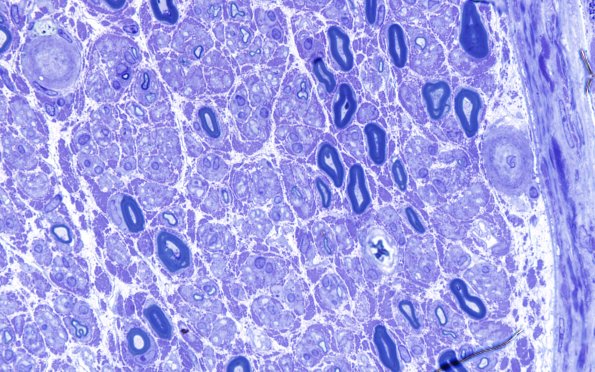

4A4 Vasculopathy (Case 4) Plastic 100X 2

Many endoneurial vessels are substantially thickened. (plastic section)